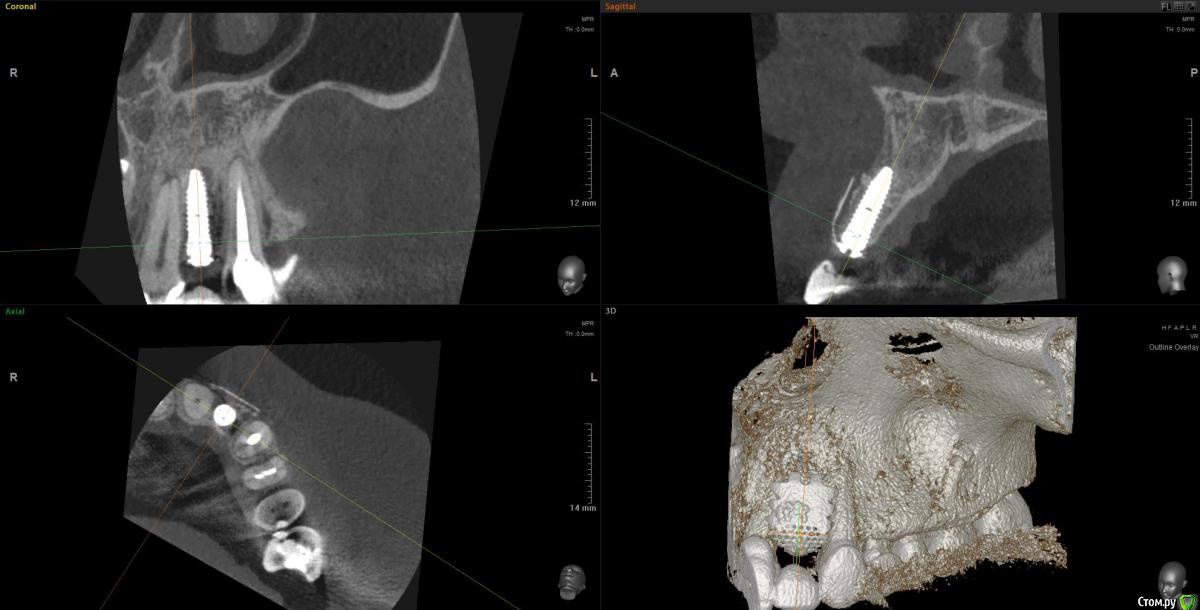

Kostoprav Опубликовано 18 сентября, 2018 Поделиться Опубликовано 18 сентября, 2018 Апатос+ ПРФ+ инъекционный ПРФ+ титановая мембрана.кт через 4,5 мес.Честно говоря кости ожидал побольше, так как паковал с гиперобобьемом. Ссылка на комментарий

stommm Опубликовано 20 сентября, 2018 Поделиться Опубликовано 20 сентября, 2018 Имхо для такого дефекта лучше сетку подлиннее (у нео есть такие) что бы апекально фиксировать в кости, а не так что апекальный край сетки лежит над дефектом. И Имплант по фото недогазлублен. Либо профиль неудачный будет, либо коронка короткая. При бОльшем заглублении имхо получилось бы лучше Ссылка на комментарий

Kostoprav Опубликовано 20 сентября, 2018 Автор Поделиться Опубликовано 20 сентября, 2018 Имхо для такого дефекта лучше сетку подлиннее (у нео есть такие) что бы апекально фиксировать в кости, а не так что апекальный край сетки лежит над дефектом. И Имплант по фото недогазлублен. Либо профиль неудачный будет, либо коронка короткая. При бОльшем заглублении имхо получилось бы лучше имплант с полированой шейкой, эго не желательно сильно погружать под кость.В инструкциях производителя этот тип мембран не предназначен для апекальной фиксации, есть мембраны с проререзями под винты но у нас таких не продают. Ссылка на комментарий

АнтонТЛТ Опубликовано 20 сентября, 2018 Поделиться Опубликовано 20 сентября, 2018 имплант с полированой шейкой, эго не желательно сильно погружать под кость.В инструкциях производителя этот тип мембран не предназначен для апекальной фиксации, есть мембраны с проререзями под винты но у нас таких не продают.Только шейка не полированная, а фрезерованная. Мембраны с прорезями это более новый вид. Мембраны без прорезей можно пробивать пином или пин/винт крепить между ножек. В вашем случае, если не прибивать, то надо было мембрану лучше загнуть или взять больший размер, чтобы мембрана опиралась на кость апикально. 2 Ссылка на комментарий